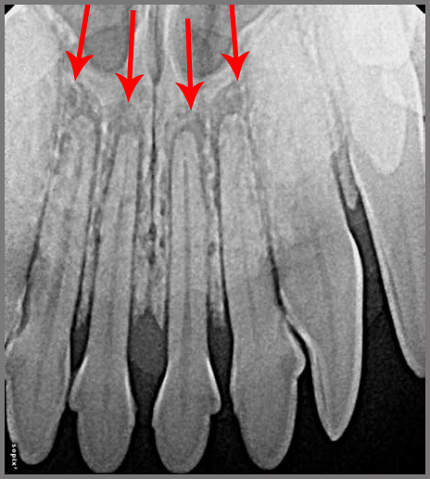

Onderstaande röntgenfoto is van een Mopshond. De ontstekingen rond de wortels van de snijtanden zijn heel duidelijk te zien (rode pijlen). De tanden zitten al los. Zulke tanden mag je als dierenarts niet in de bek achterlaten, want botontstekingen doen verschrikkelijk veel pijn.